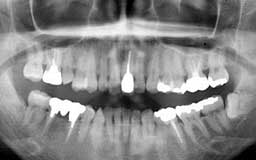

★ Oさん 61歳

Oさんもそんななかのひとりです。来院直後の6年間にブランクがあって、その時失った下

顎の前歯部を除けばかなりの状態をキープしているといえます。61歳としては余りにも条

件が良すぎたためにメインテナンスを積極的に勧めなかったことが少し悔やまれます。

| Oさん 初診時 61歳 男性 上顎臼歯部に中程度以上の歯槽骨破壊が認められるが残存する歯の数は多い |

Oさん 20年後 81歳歳 補綴(ほてつ)物が多いことに不満を感じるが親知らずを含む残存歯数27本は立派 |